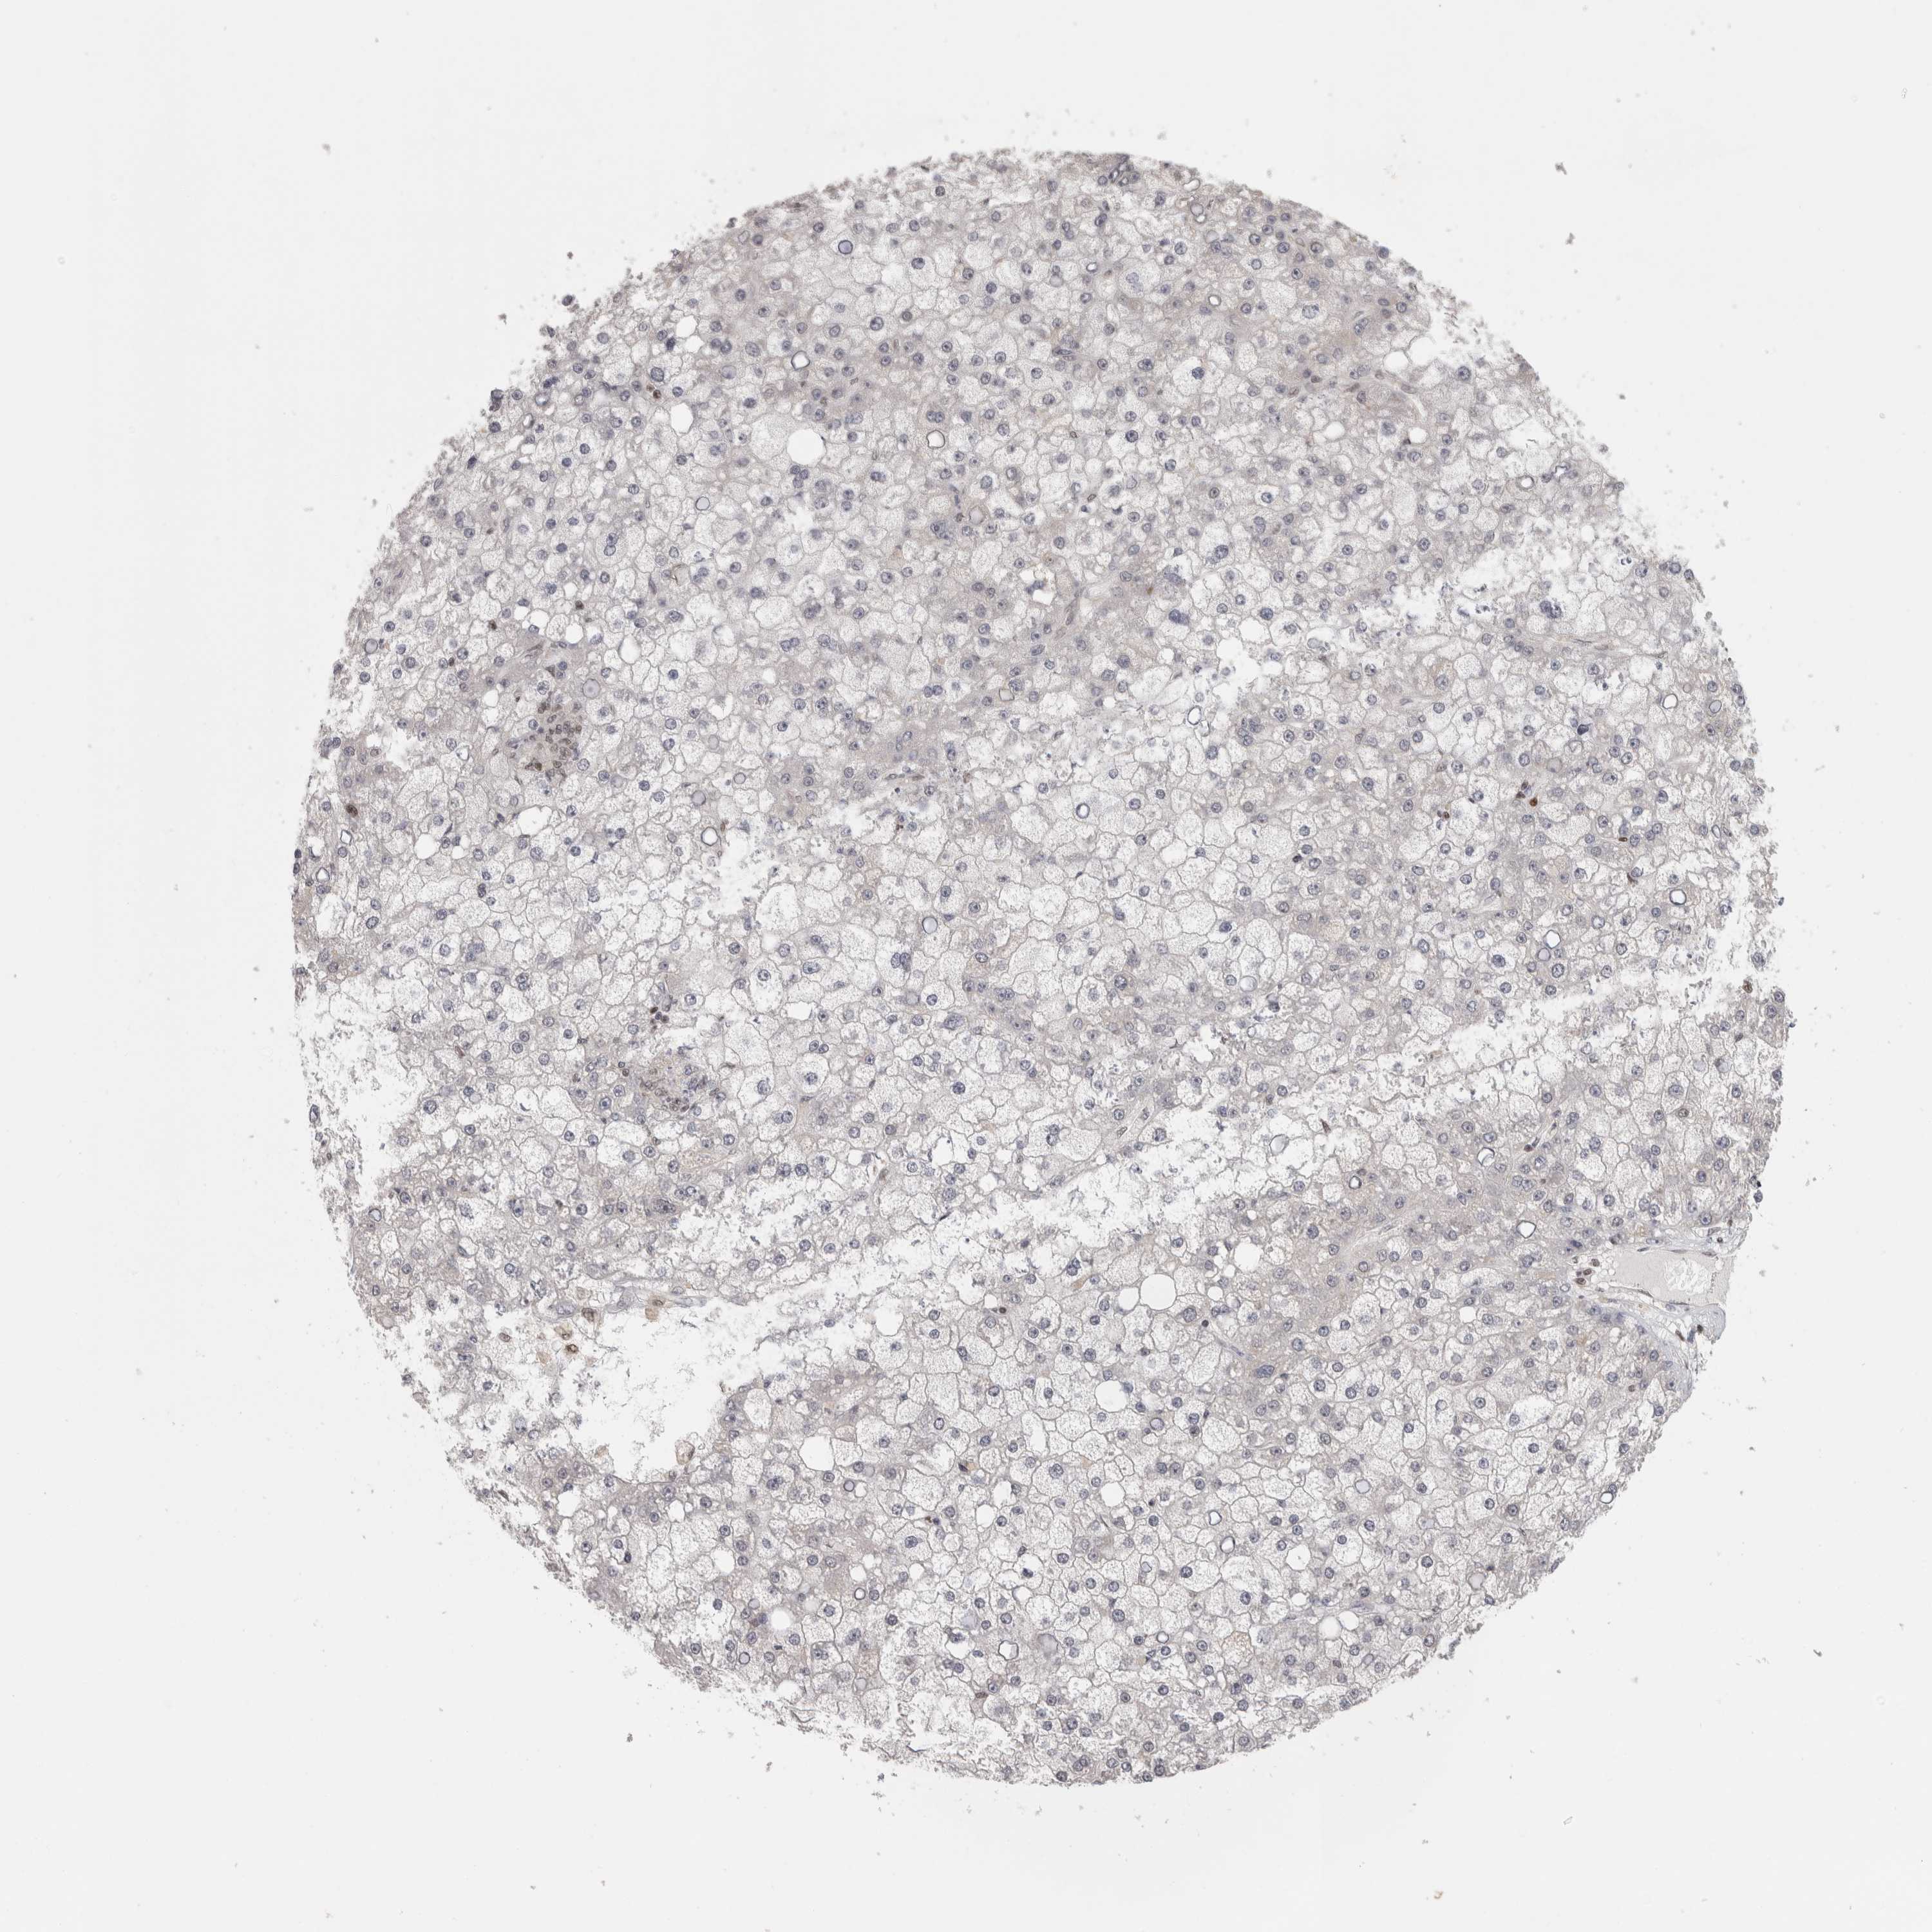

LIVER CANCER - Protein expressioni

A mouse-over function shows sample information and annotation data. Click on an image to view it in a full screen mode. Samples can be filtered based on level of antibody staining by selecting one or several of the following categories: high, medium, low and not detected. The assay and annotation is described here.

Note that samples used for immunohistochemistry by the Human Protein Atlas do not correspond to samples in the TCGA dataset.

Antibody stainingi

Antibody staining in the annotated cell types in the current human tissue is reported as not detected, low, medium, or high, based on conventional immunohistochemistry profiling in selected tissues. This score is based on the combination of the staining intensity and fraction of stained cells.

Each image is clickable and will lead to virtual microscopy that enables deeper exploration of all samples and also displays staining intensity scores, fraction scores and subcellular localization as well as patient and tissue information for each sample.

Antibody HPA026676

Staining

High

Medium

Low

Not detected

Intensity

Strong

Moderate

Weak

Negative

Quantity

>75%

75%-25%

<25%

None

Location

Nuclear

Cytoplasmic/membranous

Cytoplasmic/membranous,nuclear

Cholangiocarcinoma

Carcinoma, Hepatocellular, NOS